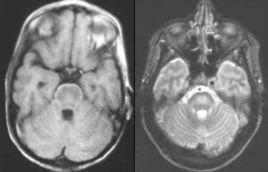

本病特徵性病理特點是,腦橋基底部呈對稱分布的神經纖維脫髓鞘,病灶邊界清楚,直徑可為數毫米或占據整個腦橋基底部,也可累及被蓋部分。神經細胞和軸索相對完好,可見吞噬細胞和星形細胞反應。